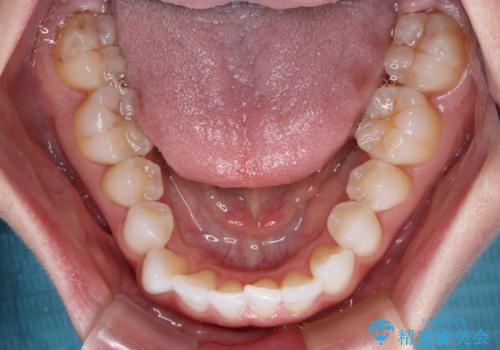

前歯のデコボコをインビザラインで綺麗に

- 上下前歯の叢生を気にして来院された患者様です。

インビザラインでの治療を希望されていて、デコボコの程度が中等度であり、安価なパッケージにて対応可能と判断されたため、インビザライン・モデレートを用いて矯正治療を行うこととしました。